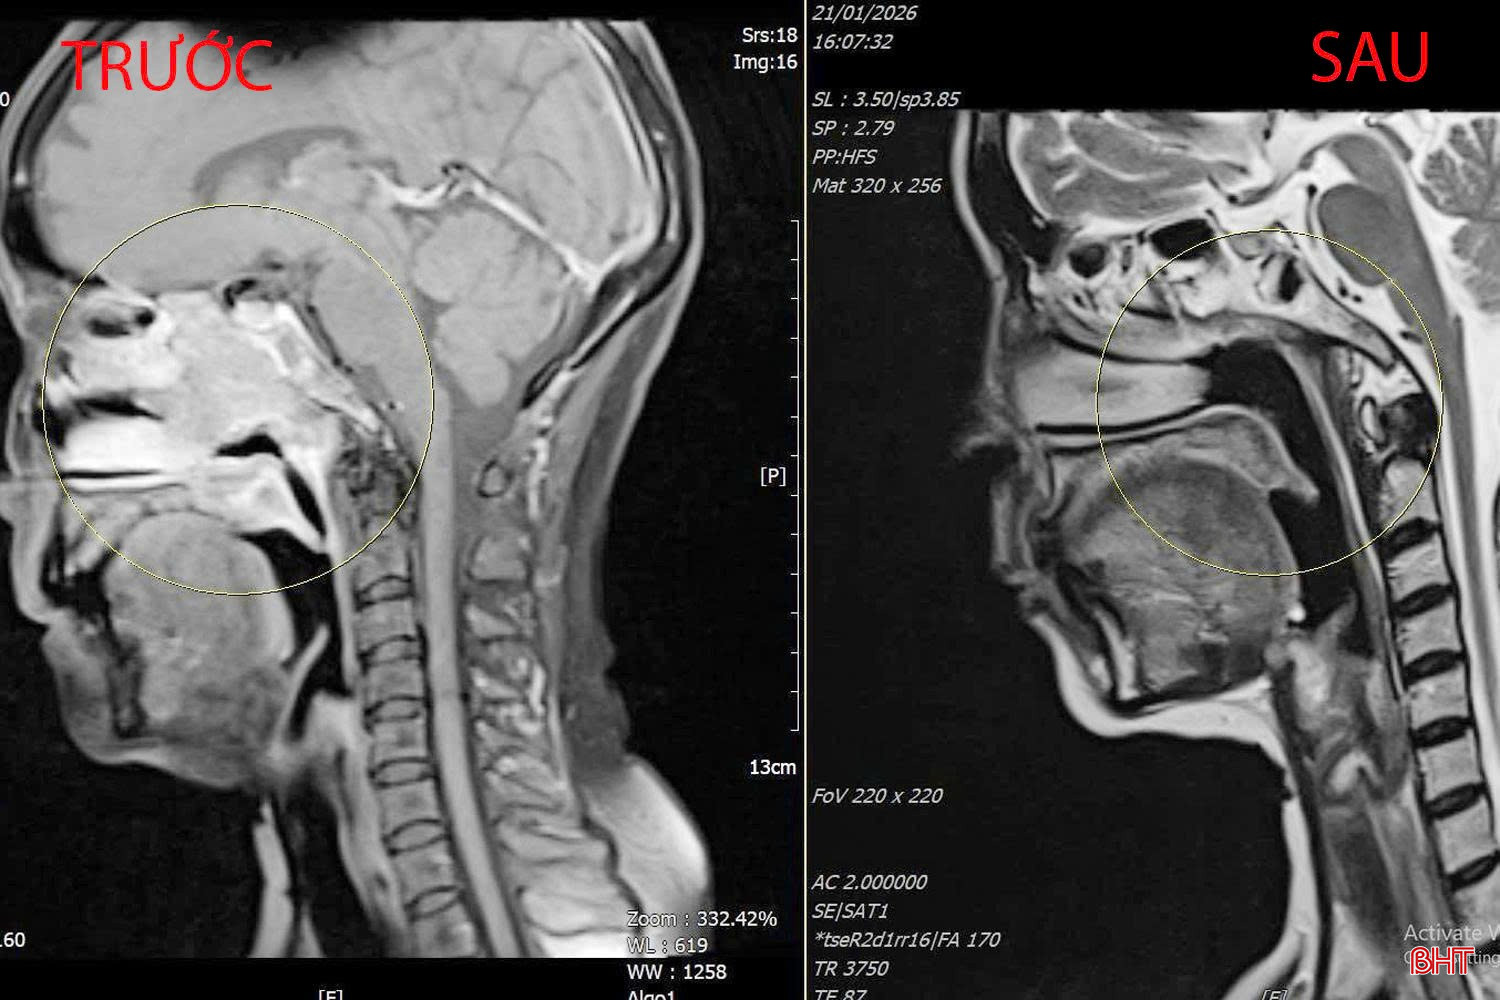

Một trường hợp khác là bệnh nhân N.T.T (63 tuổi, xã Thạch Khê) được chẩn đoán ung thư vòm họng từ năm 2022, kèm nhiều bệnh lý nền nặng như xơ gan và tiền sử xuất huyết tiêu hóa do giãn tĩnh mạch thực quản. Ngay từ thời điểm phát hiện bệnh, các bác sĩ đã tư vấn đầy đủ về nguy cơ trong quá trình điều trị, bao gồm chảy máu, vỡ khối u và xuất huyết tiêu hóa. Do lo ngại biến chứng, bệnh nhân đã từ chối điều trị.

bqbht_br_xa-tri-8.jpg

Hình ảnh khối u của bệnh nhân T. trước và sau khi triển khai xạ trị.

Tuy nhiên, gần đây, bệnh nhân đã phải nhập BVĐK tỉnh trong tình trạng thường xuyên chảy máu mũi và vòm họng, nguyên nhân do khối u vòm phát triển và xâm lấn, nguy cơ vỡ, đe dọa trực tiếp đến tính mạng. Trước tình trạng nguy cơ xuất huyết nghiêm trọng do vỡ khối u, trên nền xơ gan, giảm tiểu cầu nặng, các bác sĩ Khoa Ung bướu – Y học hạt nhân đã tiến hành hội chẩn chuyên môn và quyết định triển khai xạ trị kỹ thuật cao điều biến liều (IMRT) tập trung vào khối u vòm, với mục tiêu kiểm soát chảy máu và bảo vệ an toàn cho người bệnh. Sau 1 tháng điều trị, kết quả đánh giá cho thấy khối u đáp ứng tốt, tình trạng chảy máu được kiểm soát hiệu quả. Bệnh nhân thoát khỏi nguy cơ nguy hiểm do vỡ khối u vòm, sức khỏe dần ổn định, chất lượng cuộc sống được cải thiện rõ rệt.